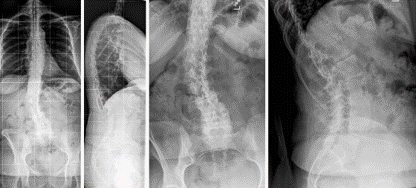

图7 术前-术后1个月-术后1个月外观